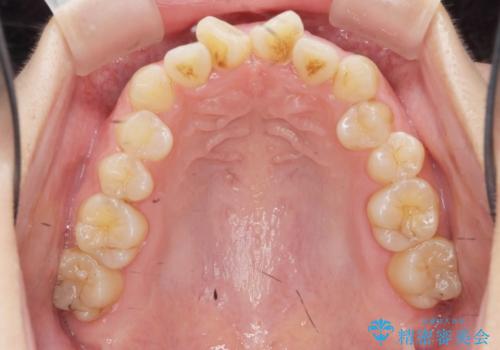

前歯のねじれをマウスピース矯正インビザラインで治療

- 長年気になっている、前歯のねじれの矯正治療を希望され来院されました。

十分にマウスピース矯正インビザラインで治療が可能と判断し、治療を進めることとしました。

長年気になっていた前歯のねじれが、ワイヤーをつけることなく矯正を行うことができ、大変喜んでいただくことができました。